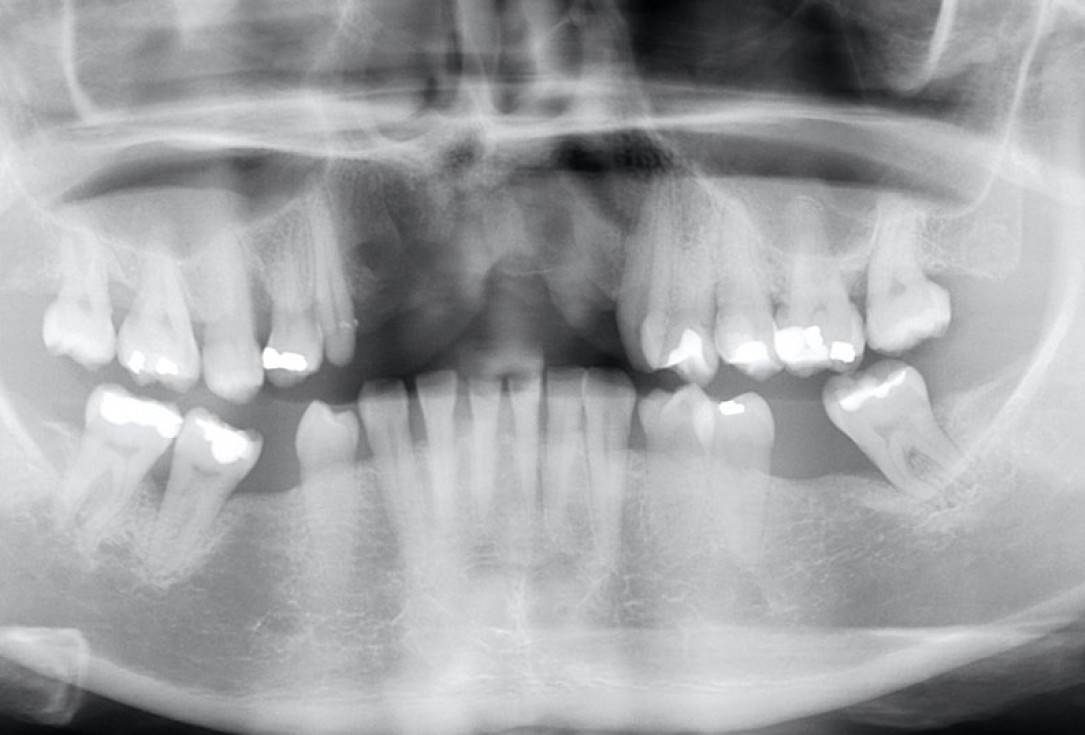

4/17 - X-ray scan after extraction of failing implantsRestoration of all four incisors with maxgraft® bonebuilder - Dr. Dr. Dr. O. Blume